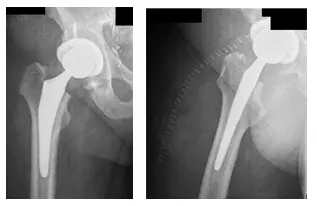

Tras la revisión, las radiografías mostraron que el paciente tenía artritis de cadera derecha, como se muestra a continuación. Se discutieron a fondo las opciones con el paciente junto con el riesgo, los beneficios y cualquier alternativa, pero se aconsejó que el paciente recibiera una artroplastia total de cadera derecha (ATC) debido a sus signos y síntomas actuales.

La paciente había decidido someterse a una ATC derecha. Debido a sus antecedentes de cáncer, se habló largo y tendido con el paciente de que presentaba un mayor riesgo de trombosis venosa profunda (TVP) y embolia pulmonar (EP).

Las radiografías muestran una artroplastia total de cadera derecha con una buena colocación de la prótesis